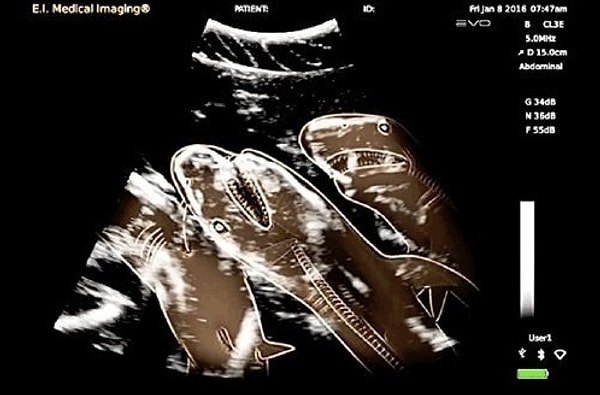

7. УЗИ беременной акулы